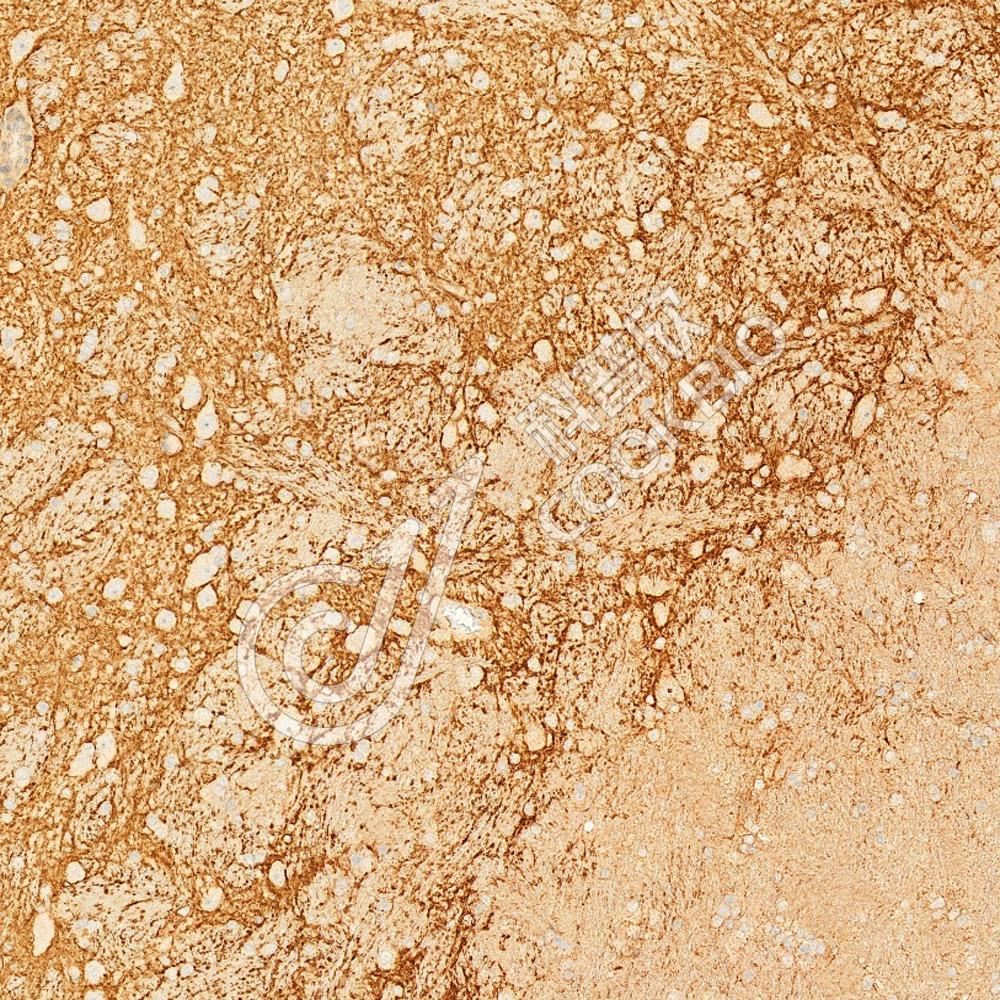

IHC检测GABA Transporter 3/GAT 3蛋白(货号 K1345327).

样品: 小鼠脊髓, 4%多聚甲醛 (货号KSG1101) 固定12-24小时.

抗原修复: Tris-EDTA抗原修复液(pH 9.0) (KSG1203), 98℃, 20分钟.

—抗: 1: 1300稀释, 4℃ 孵育过夜.

二抗: S-vision免疫组化多聚二抗(山羊抗兔),即用型 (货号KB3906), 室温孵育20分钟.

样品: 大鼠脑, 4%多聚甲醛 (货号KSG1101) 固定12-24小时.